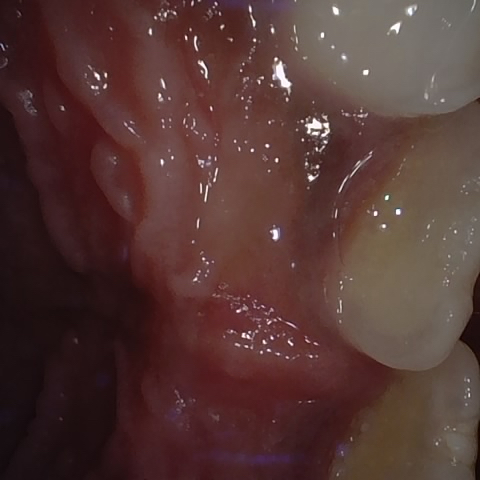

Annotated as "Good"